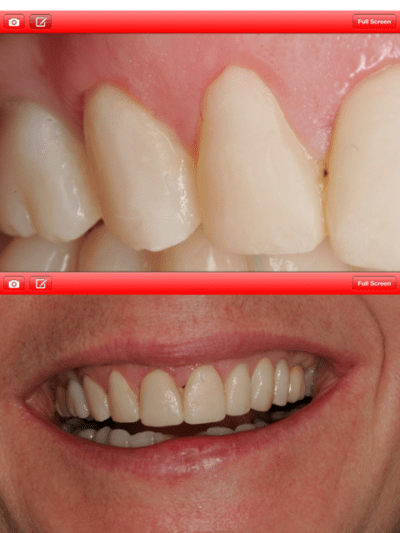

Voila c'est fini, mais je suis critique sur plusieurs points:

- La qualité des CCM qui est pas super mais faite par le labo qui ma référé la patiente.

- La 11 dont le collet s'est un petit peu rétracté et laisse apparaître la racine par transparence. J'aurais souhaité faire un lambeau tracté coronairement , mais pas la patiente qui est très satisfaite.

- Le collet de la 22 trop apical, à cause de l'élongation coronaire trop apicale.

Merci pour ce partage. Je retiens un très joli travail de chirurgie plastique pour l'esthétique rose: et je serais moins critique que toi pour 11 et 22, car il suffit de voir ton cliché du sourire ( aux éclats), pour apprécier l'intégration paro de tes éléments prothétiques.

Je partage ton avis pour le prothésiste (dommage), autant sur le montage céramique que sur l'animation d'ailleurs.

Je regrette par contre que tu ais gardé la 16 en l'état (ça jure un peu dans le sourire).

Le bas fait un peu "bloc", ce doit être du composite, la patiente bruxe t- elle toujours?